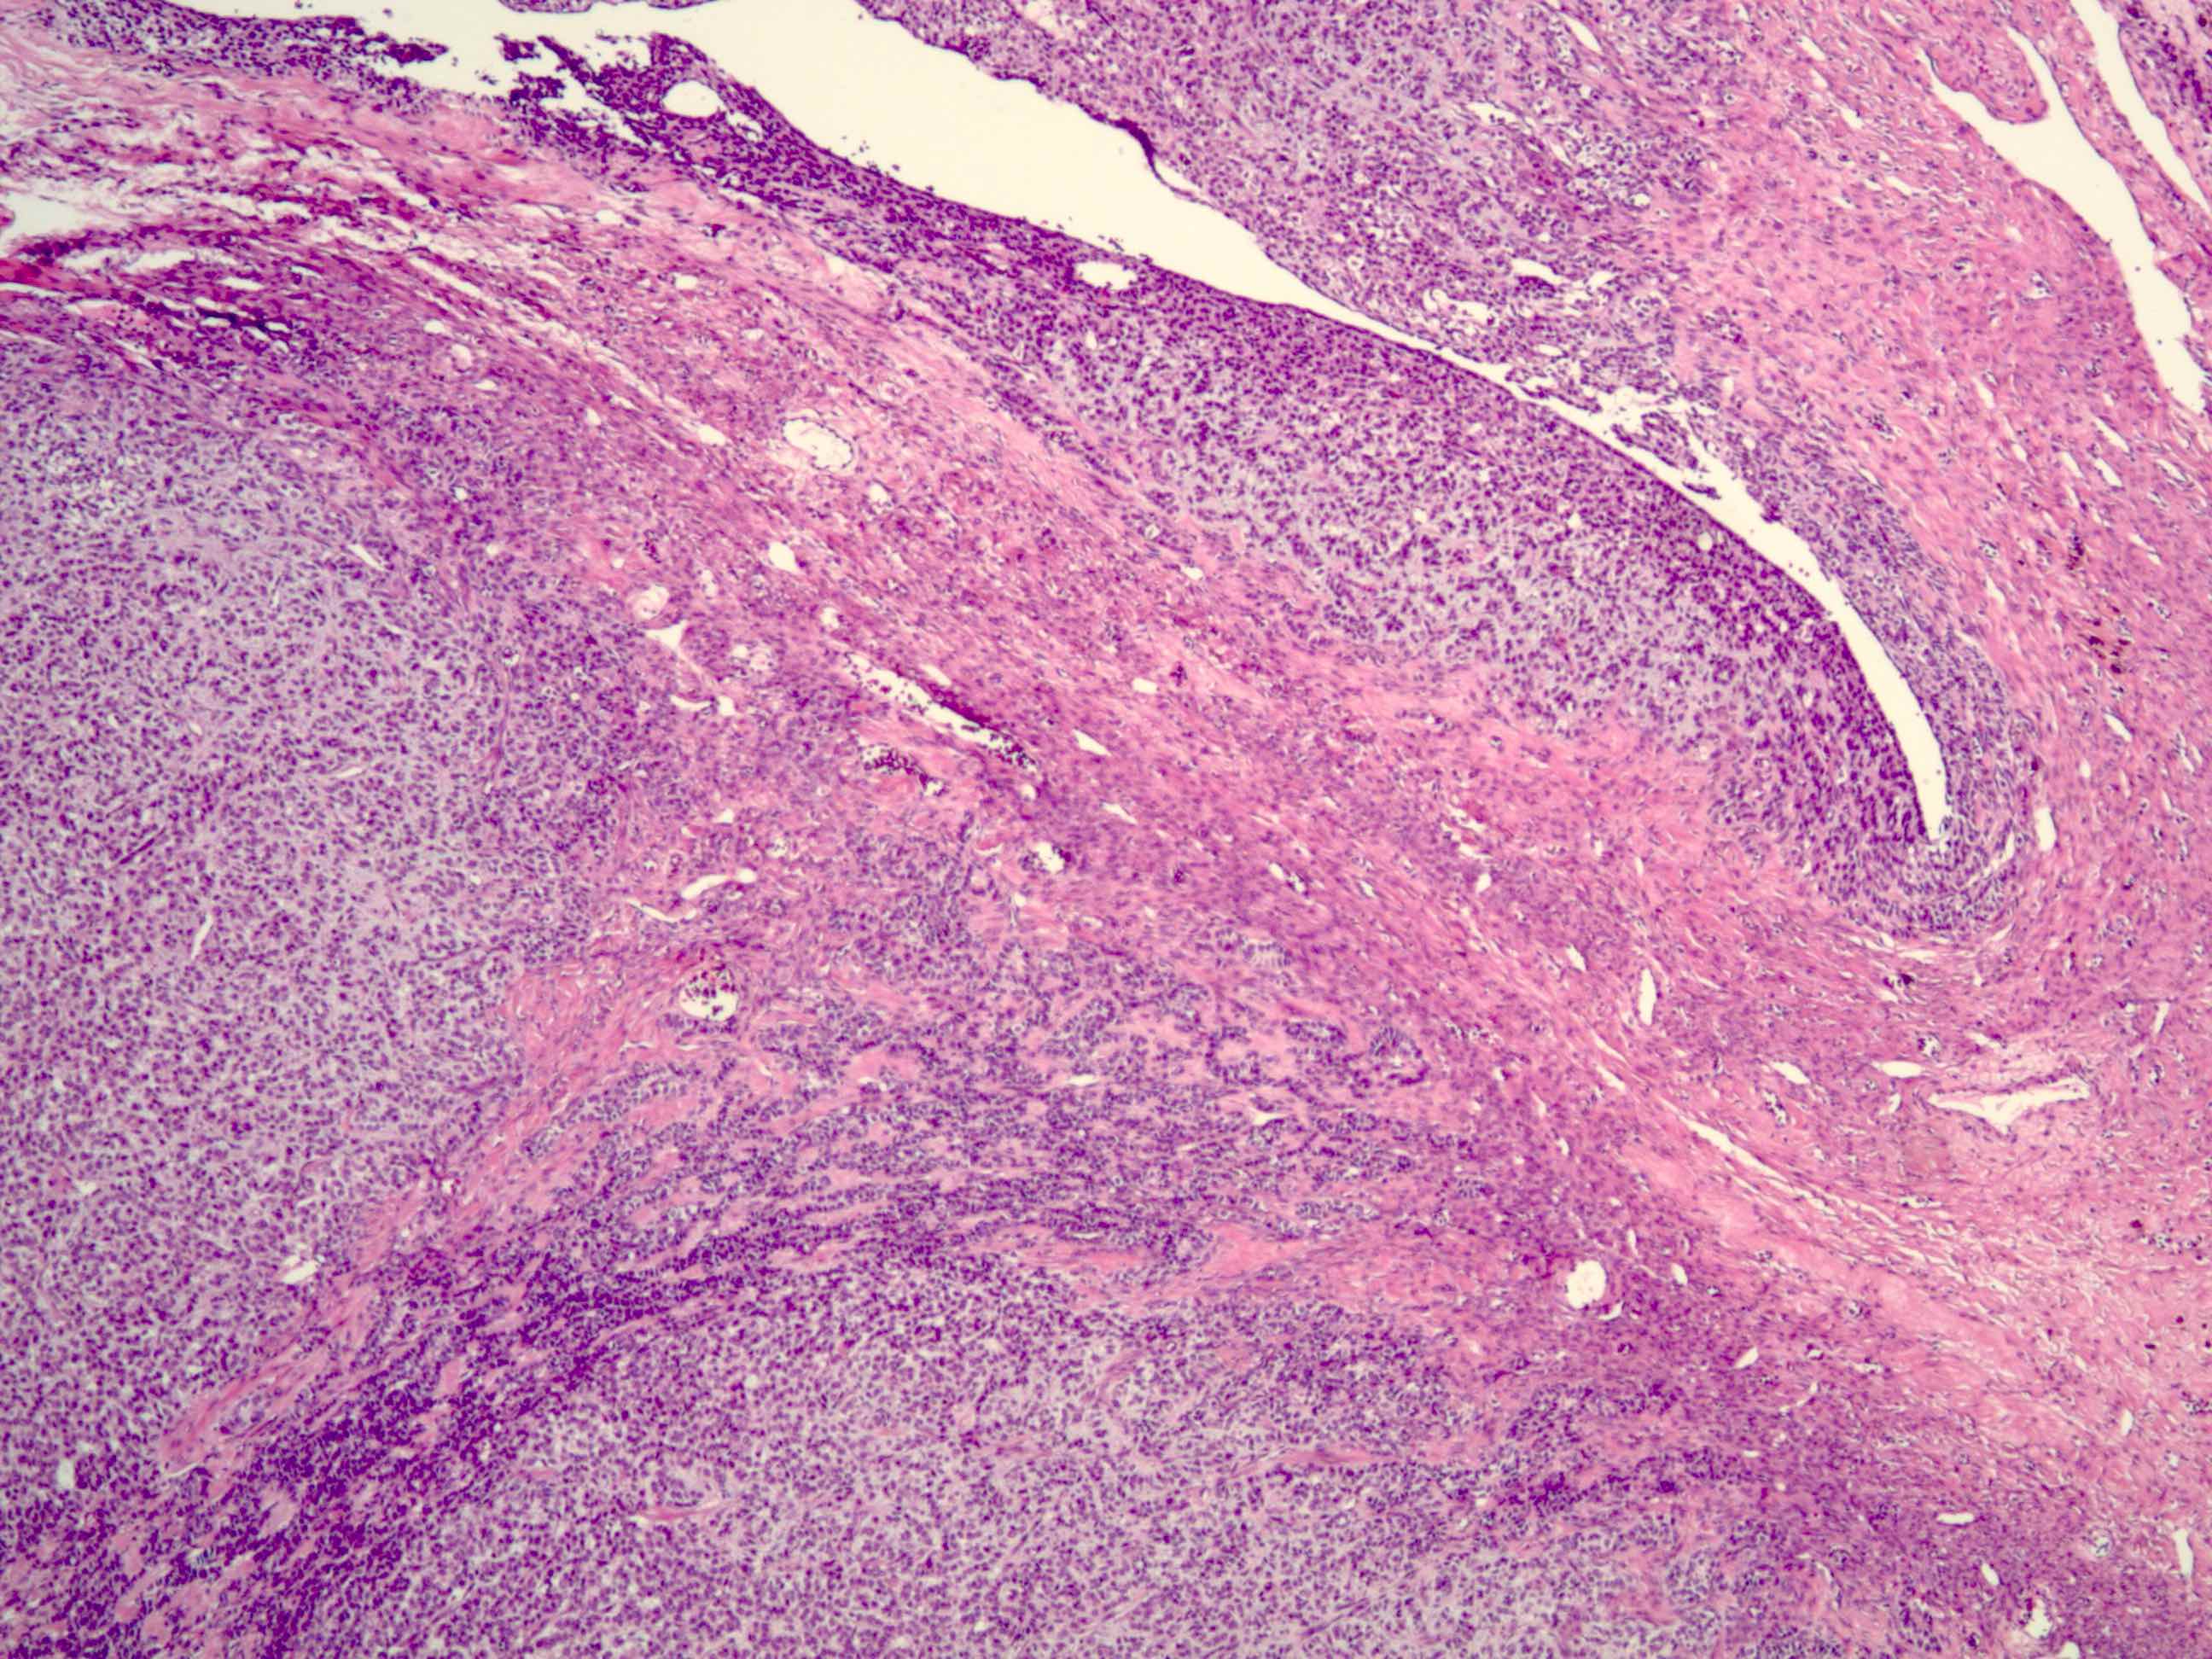

- Various patterns, including diffuse (the most common), trabecular and corded, insular, microfollicular (resembling Call-Exner bodies of the Graafian follicles: small follicle-like structures filled with eosinophilic material) and macrofollicular (the least common)

- Usually a mixed growth pattern is seen

- Stroma is usually hypervascular with variable amounts of fibroblasts and theca cells

- Theca cell proliferation is considered a stromal response rather than a second population of tumor cells (granulosa - theca cell tumor)

- Can have a prominent fibrothecomatous stroma; need 10% granulosa cells to be classified as adult granulosa cell tumor, otherwise best classified as thecoma or fibroma with minor sex cord elements

Microscopic (histologic) images

Contributed by Shabnam Zarei, M.D. and Sharon Bihlmeyer, M.D.

AFIP images